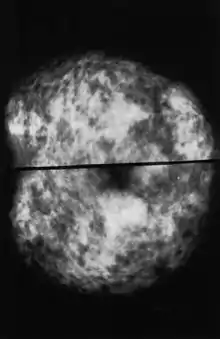

Molecular breast imaging

Molecular breast imaging is a nuclear medicine technique that is currently under study. It shows promising results for imaging people with dense breast tissue and may have accuracies comparable to MRI.[43] It may be better than mammography in some people with dense breast tissue, detecting two to three times more cancers in this population.[43] It however carries a greater risk of radiation damage making it inappropriate for general breast cancer screening.[44] It is possible to reduce the dose of radiation used.[45]

An earlier alternative technique suited to dense breast tissue, scintimammography is now not recommended by the American Cancer Society, which states, "This test cannot show whether an abnormal area is cancer as accurately as a mammogram, and it's not used as a screening test. Some radiologists believe this test may be helpful in looking at suspicious areas found by mammogram. But the exact role of scintimammography is still unclear."[46]